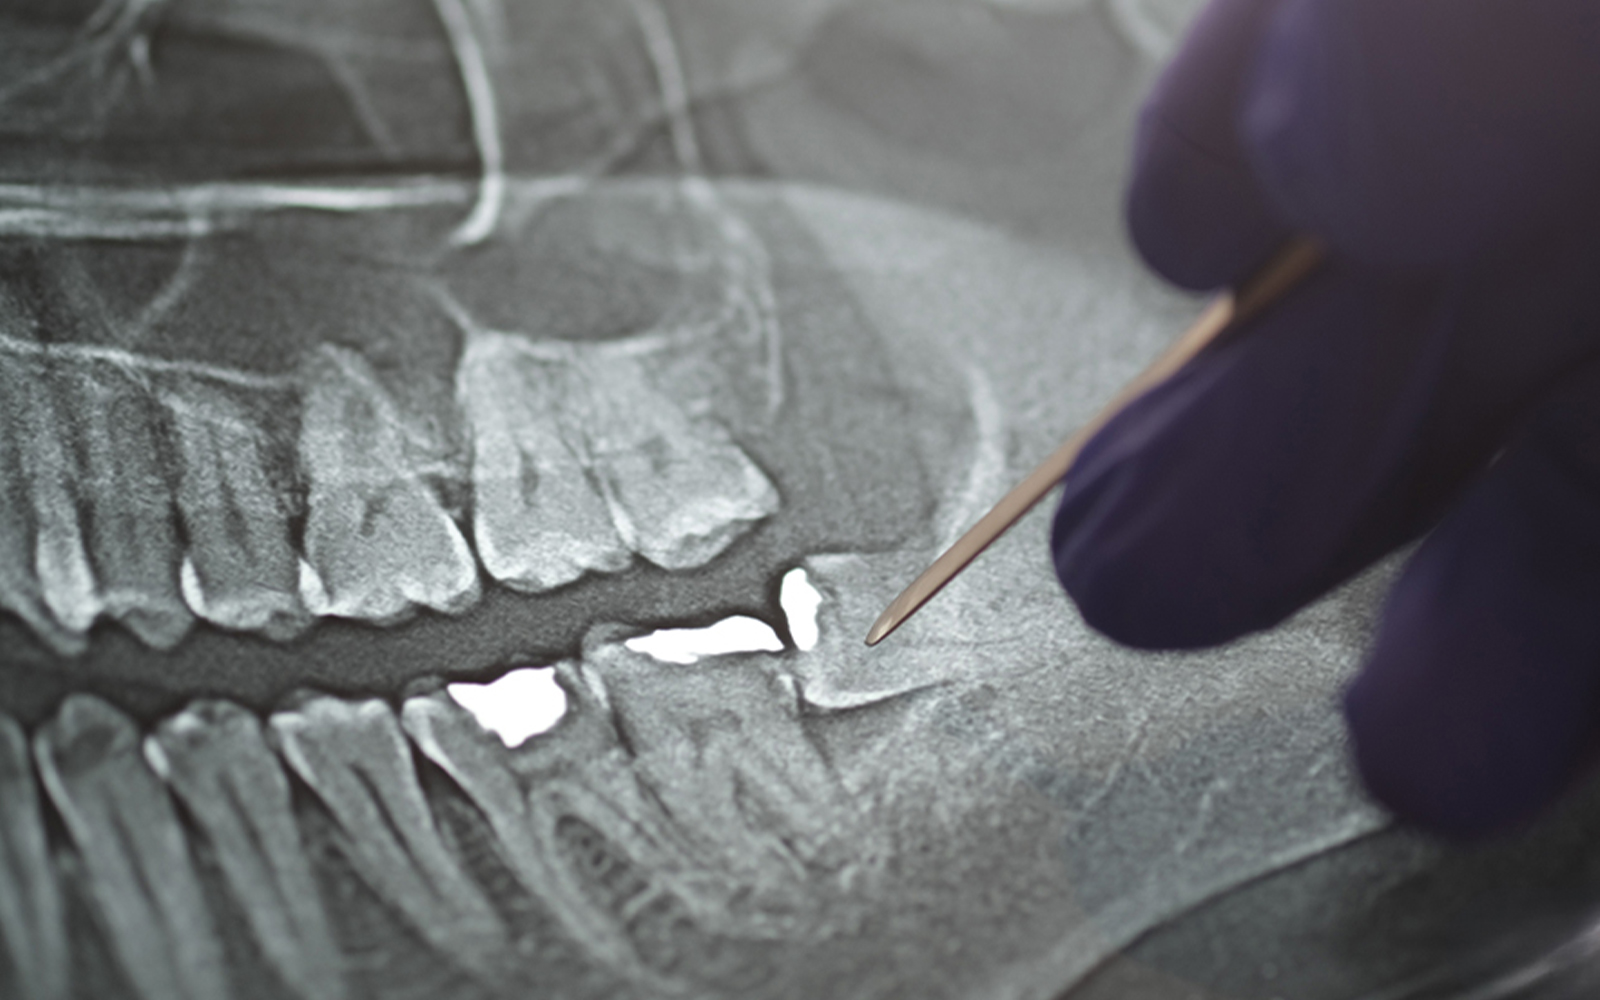

• レントゲン写真(紹介状に添付または別途提供)

検査:必要に応じて、お口の中の検査やレントゲン、写真撮影を行います。